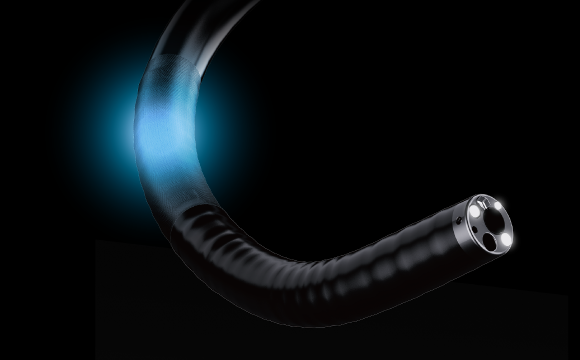

Синхронизация передачи усилияИнерционная конструкция во вводной части колоноскопа. Во время обследования он может передавать толкающие, вытягивающие и вращательные усилия, прилагаемые оператором к рукоятке, на дистальный конец колоноскопа, способствуя лучшему введению в цекум. 3 СветоводаИнновационная система подсветки тремя светододами на дистальном конце обеспечивает более масштабное и равномерное освещение во время проводения процедур. В сочетании с широким полем обзора это обеспечивает высочайшее качество изображения.

3 СветоводаИнновационная система подсветки тремя светододами на дистальном конце обеспечивает более масштабное и равномерное освещение во время проводения процедур. В сочетании с широким полем обзора это обеспечивает высочайшее качество изображения.